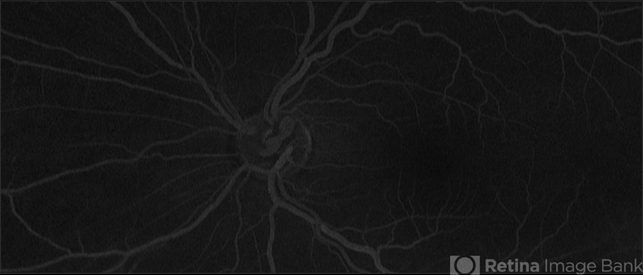

- HTN Retinopathy with Prepapillary vascular loop

- prepapillary vascular loop, congenital prepapillary vascular loop, congenital prepapillary vascular anomaly

Scanning laser ophthalmoscope

Optos California - Description

- Late phase, ultra-wide fluorescein angiogram of a 53-year-old, African American male with history of diabetes, hypertension, depicting chronic hypertensive retinopathy changes and unilateral pre-papillary vascular loop OS.